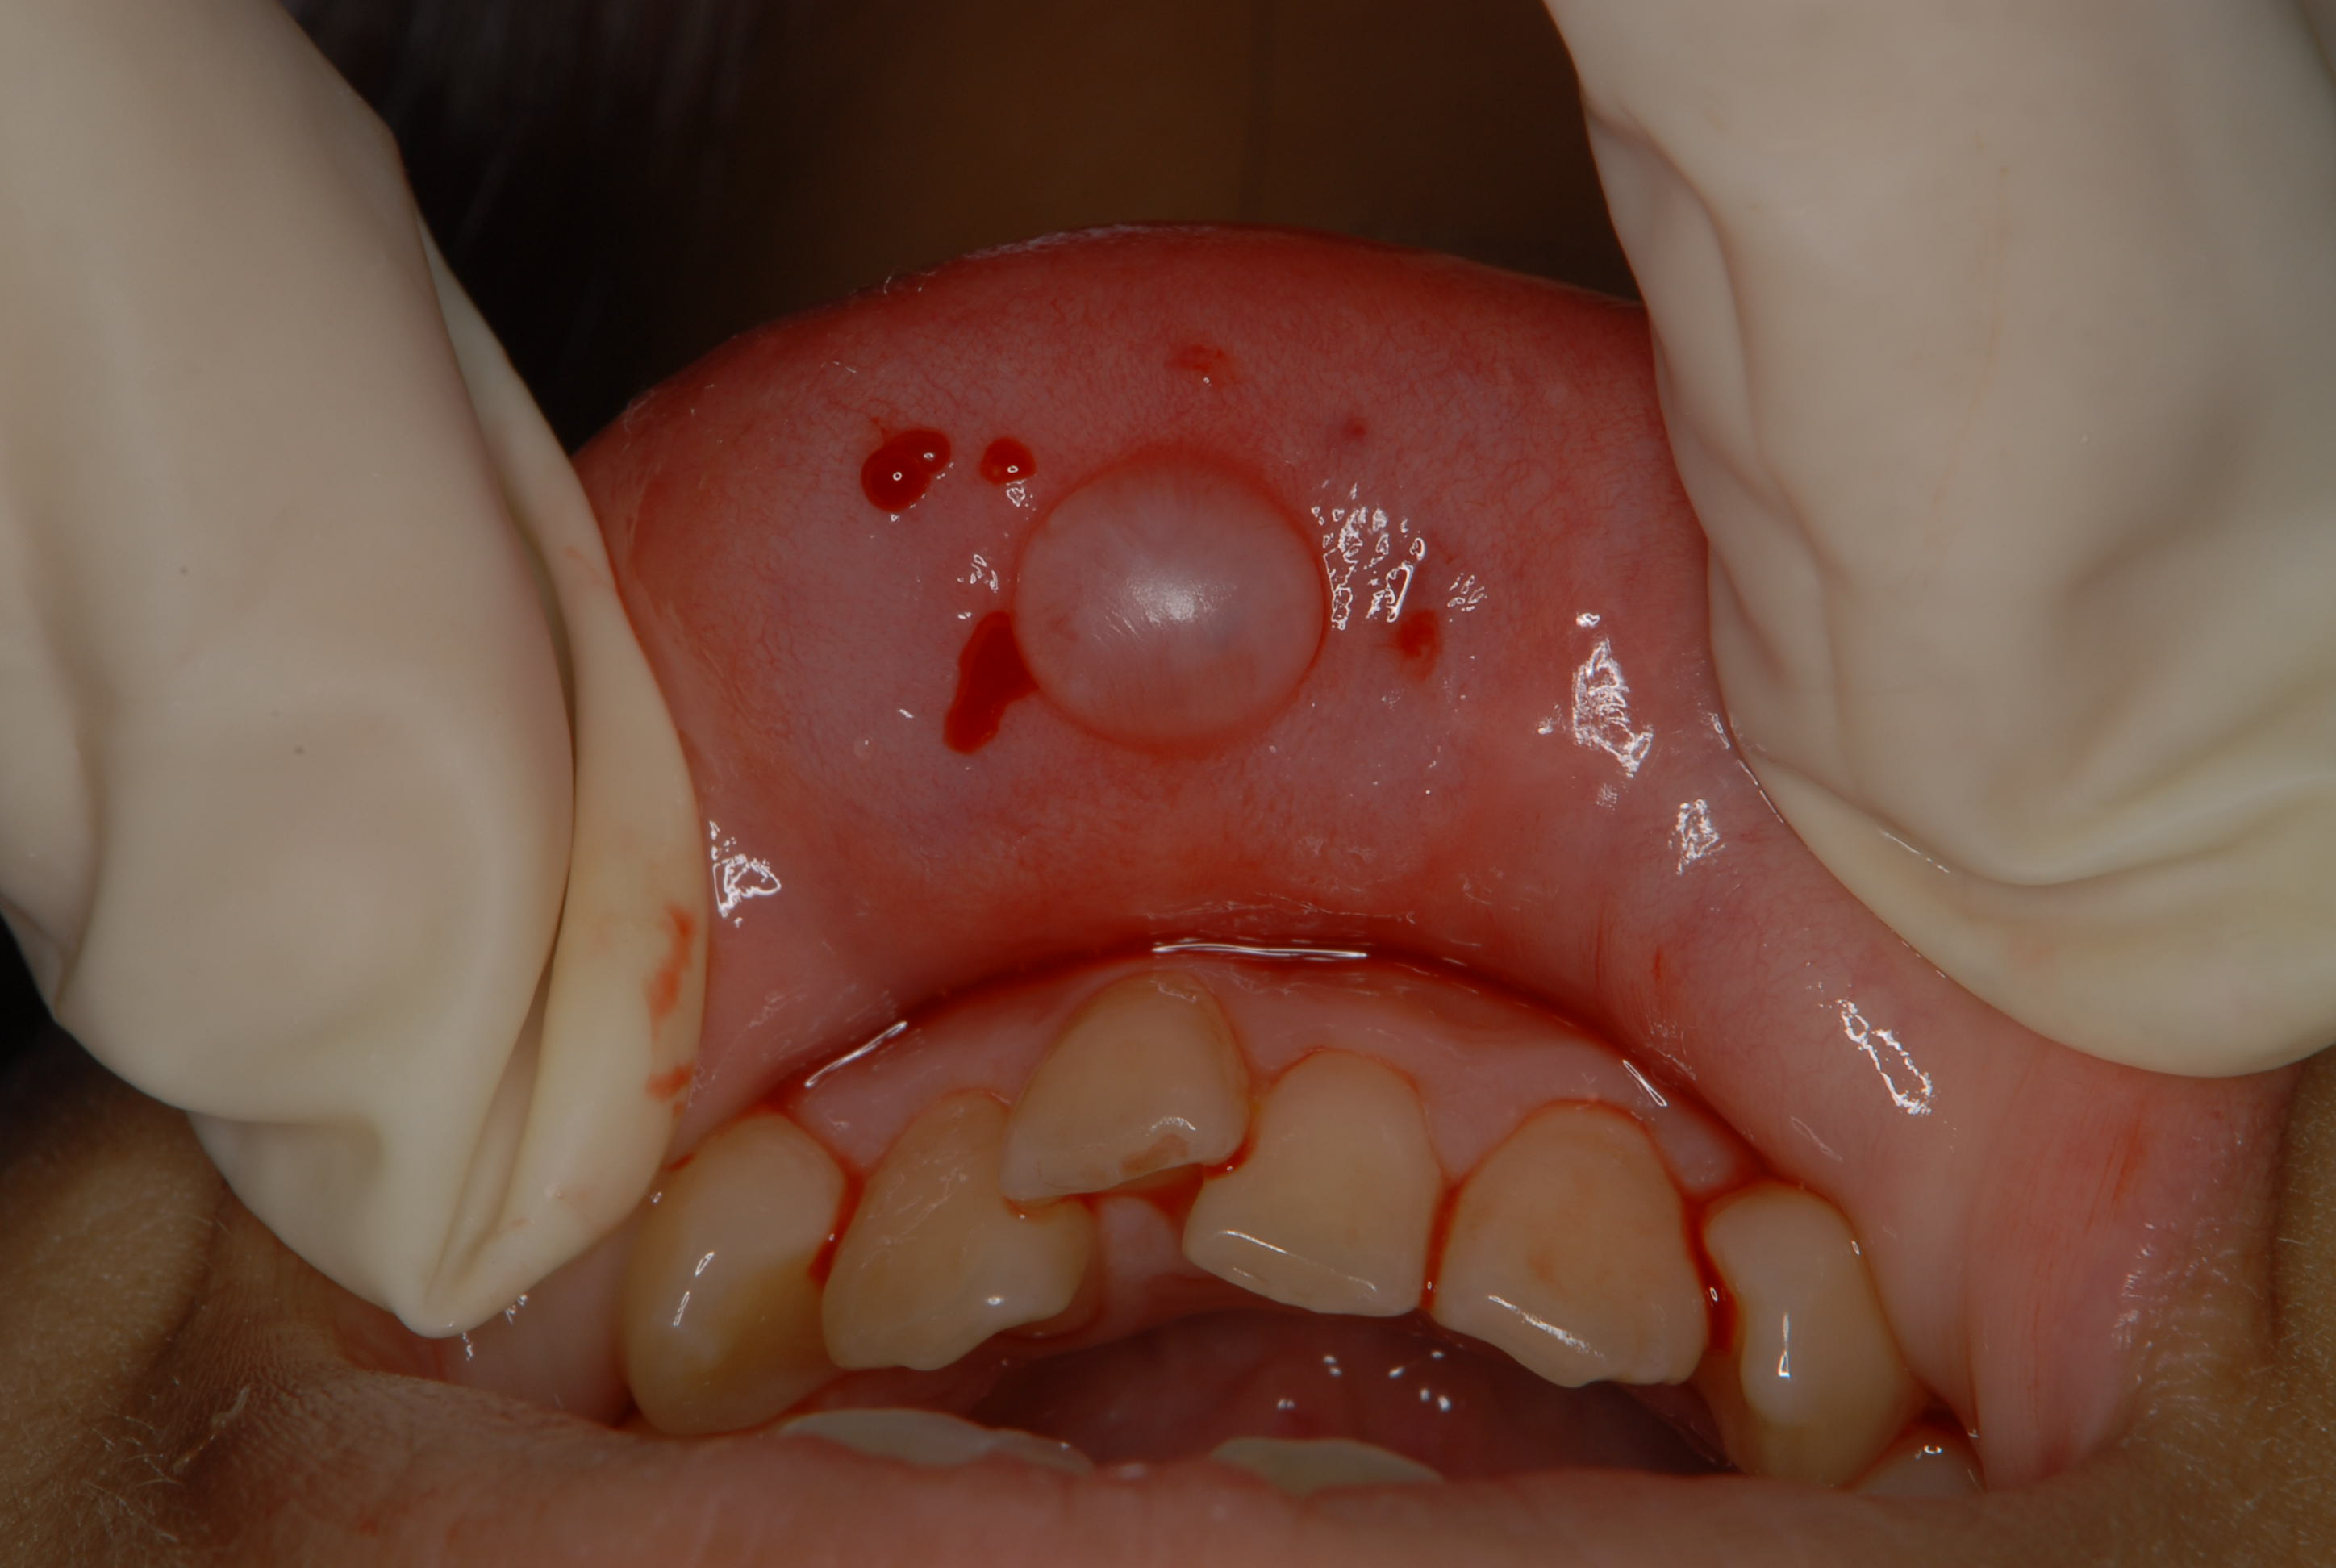

自然に消滅することもありますが、写真のように大きくなると